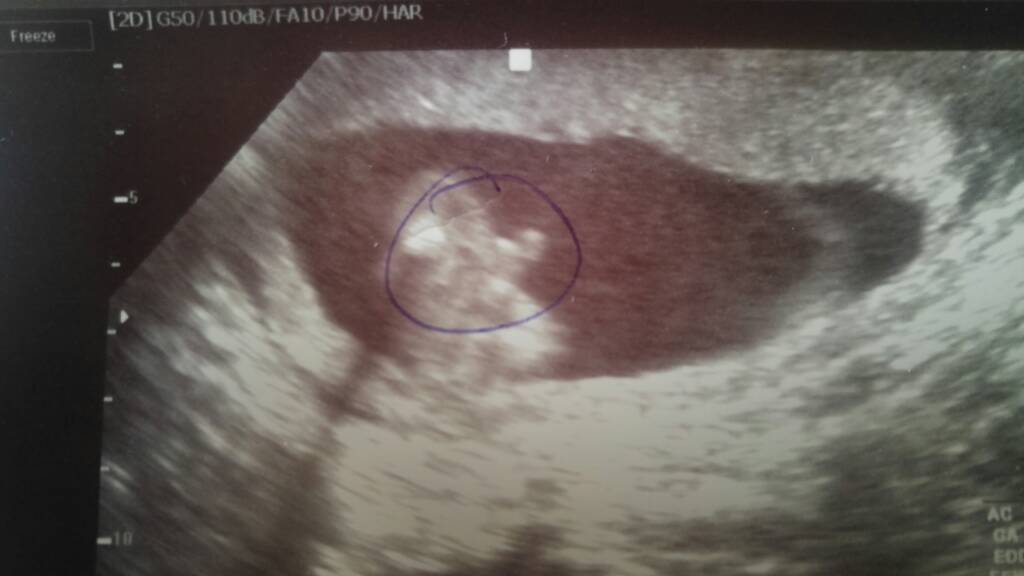

U nas po wizycie wszystko dobrze :) Maluch zdrowy i wszystko na miejscu jest :) Mamy chłopaka :) cieszymy się strasznie :) Na tarczycę dostałam euthyrox 100, duphaston profilaktycznie mam brać dalej, a co do seksu możemy spróbować jak się nic nie będzie działo po, to możemy a jak coś to zaprzestać ;) Cytologię mi pobrała jeszcze.